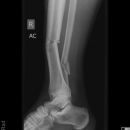

distaler Unterschenkelschaft

Spiralfraktur Tibia